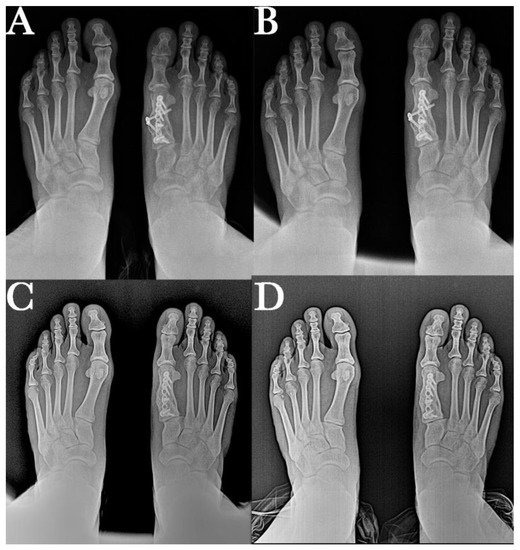

2. Case Report

2.1. Surgical Procedure

2.2. Postsurgical Procedure and Evolution

2.3. Results